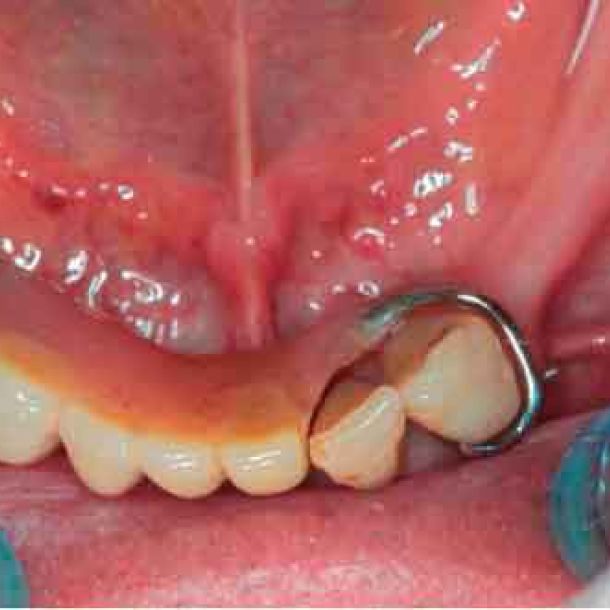

Picture - Initial bite situation

3D models - Bite scan from intra-oral scanner